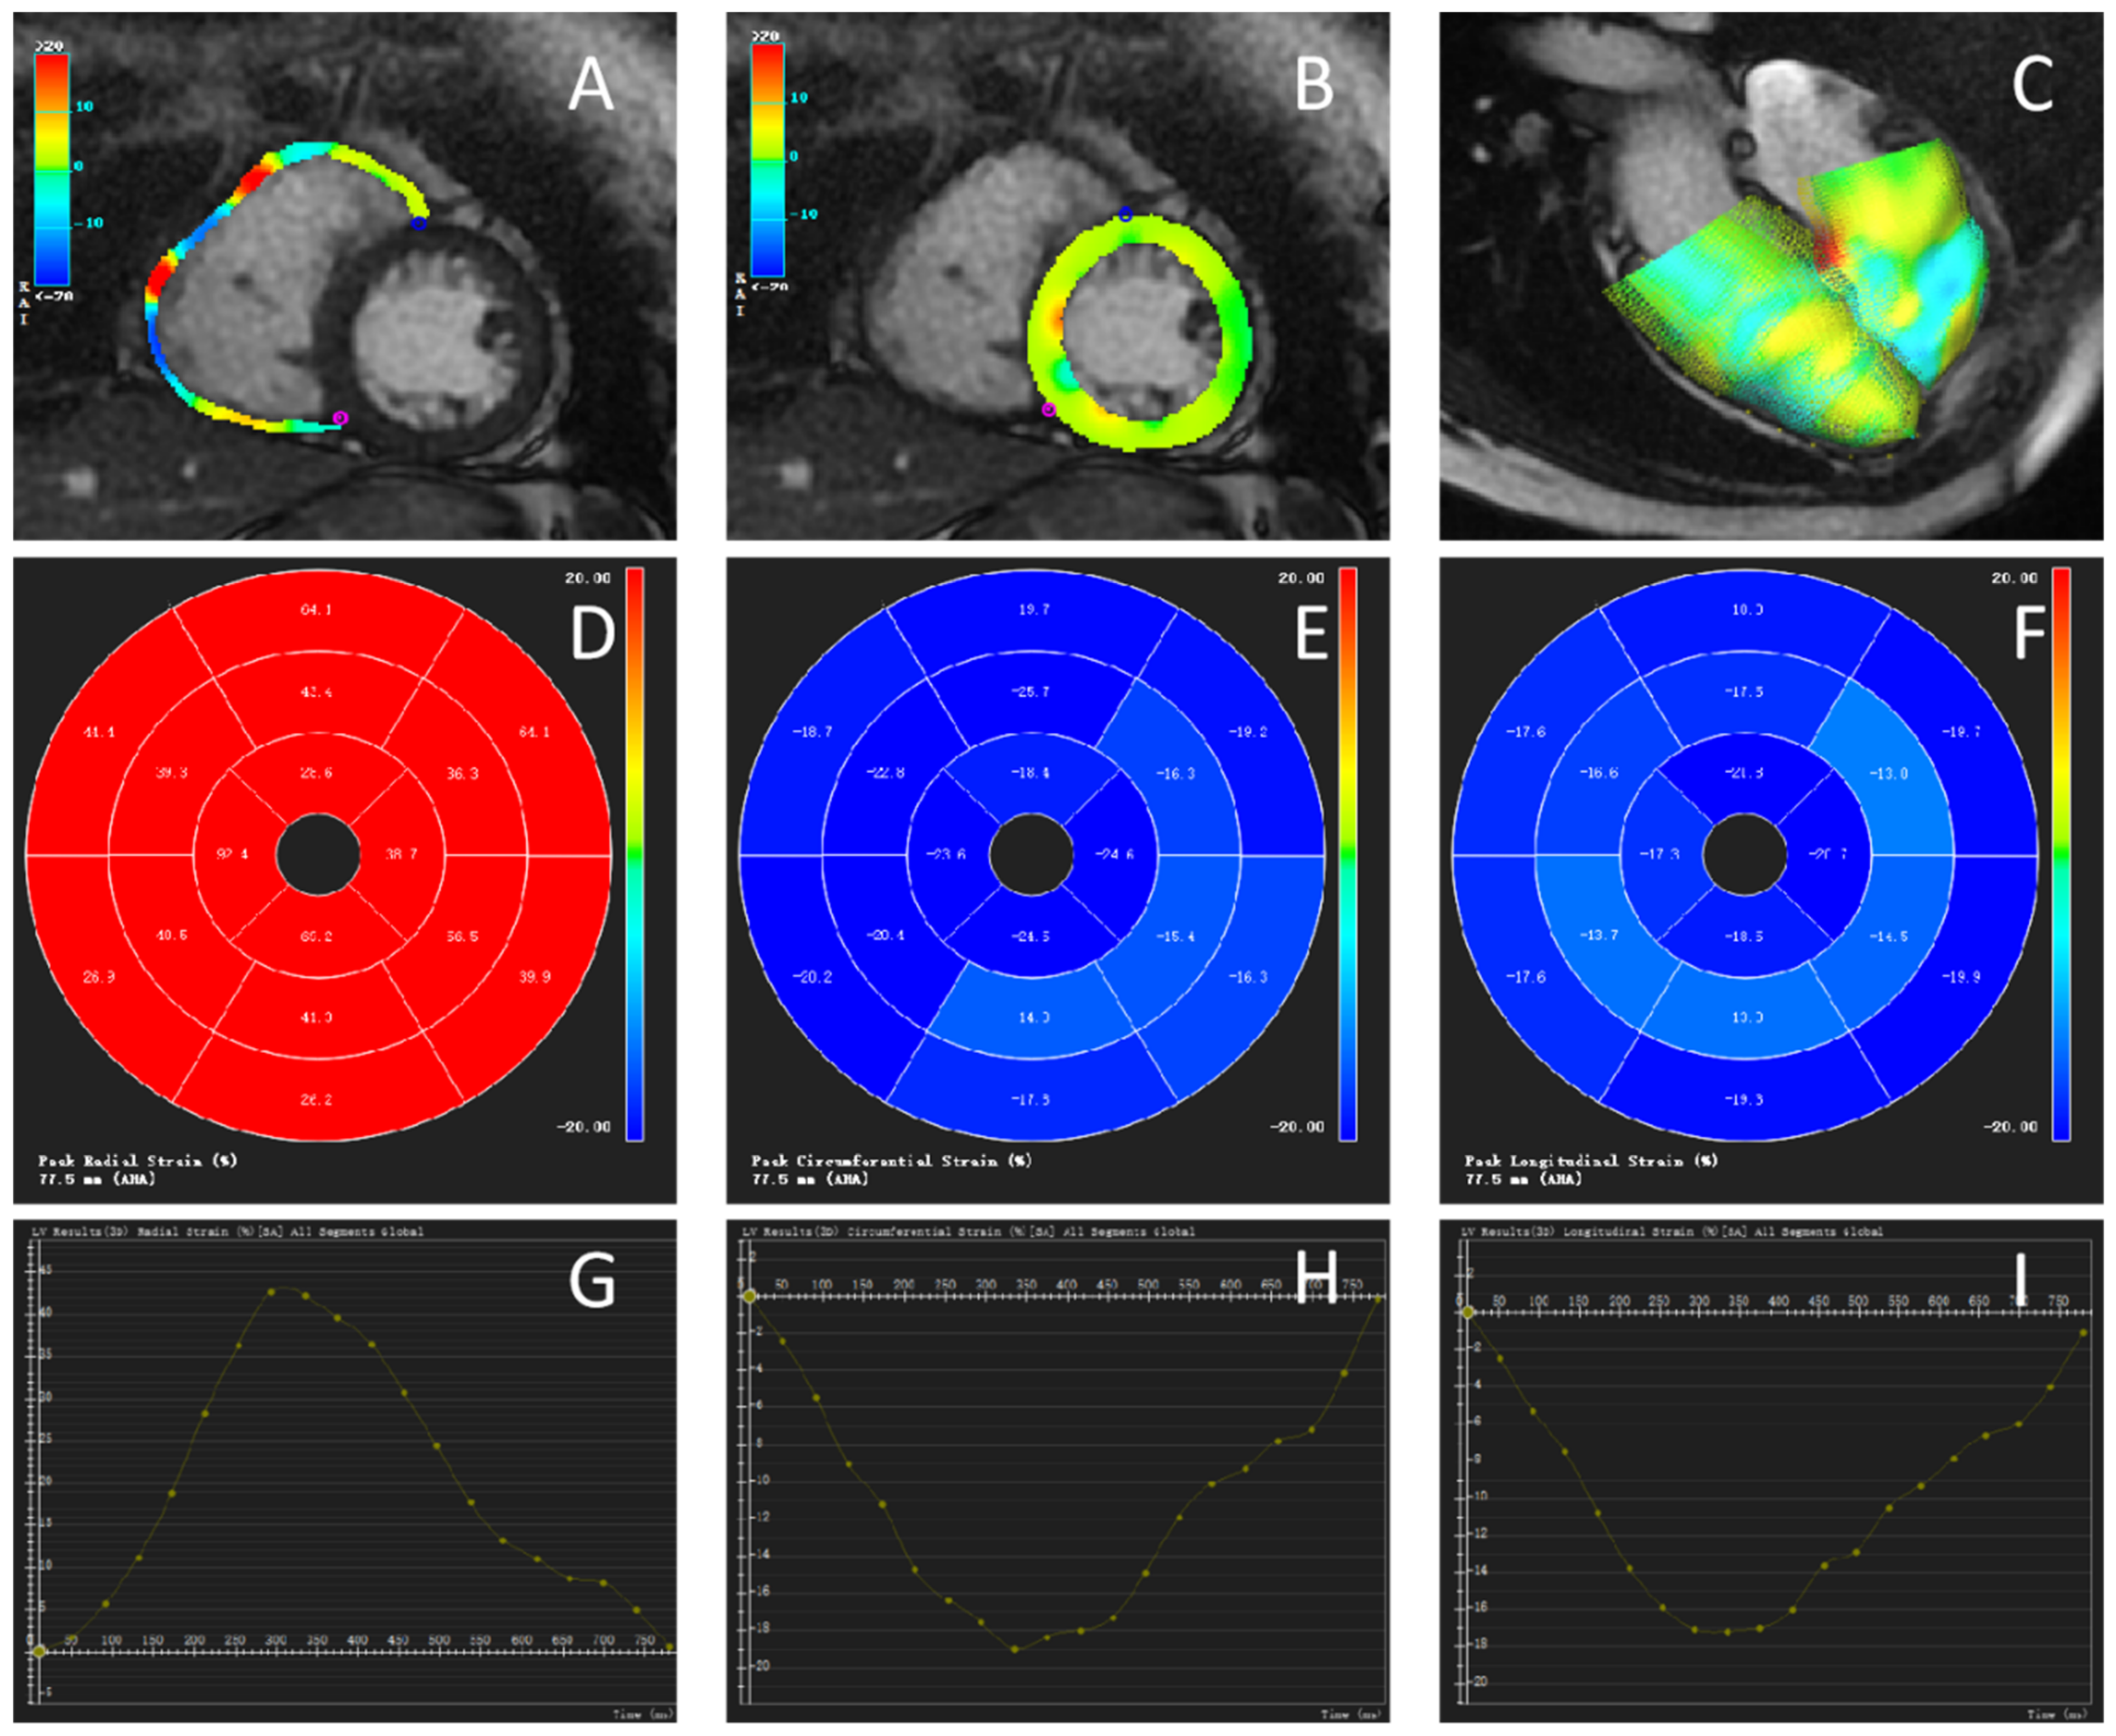

2.3.2. Myocardial Strain Parameters

Biventricular myocardial strain parameters were measured using the CVI42 TT technique. The investigators selected the diastolic phase of the left ventricle, semiautomatically outlined the endocardium of both ventricles, marked the septum in the short-axis view of both ventricles, marked the valve plane and apical position in the standard four-chamber view and the two-chamber view of the left ventricle, and then automatically generated the 2D strain parameters and strain curves of both ventricles, as shown in Figure 2.

Figure 2.

Cardiac magnetic resonance tissue tracking (CMR-TT) in the same patient with PAH shown in Figure 1. (A–C) Global radial strain of the ventricles in diastole. Color coding represents the tracking for the ventricle. (A) Right ventricle. (B) Left ventricle. (C) 3D model of the left and right ventricles in diastole. The color coding represents the epicardial contours. (D–F) Polar map of 2002 American Heart Association segmentation. (D) Radial strain (RS). (E) Circumferential strain (CS). (F) Longitudinal strain (LS). (G–I) Curve showing the strain values of the left ventricle in 25 phases, including the peak value. (G) RS. (H) CS. (I) LS.